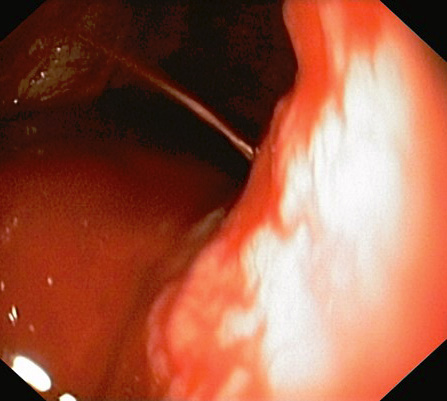

A 55-year-old male patient arrived at the Emergency Department of the Republican Vilnius University Hospital complaining of black stools and general weakness for only 1-day, tachycardia and low arterial blood pressure. UGIB was suspected. An extra esophagogastroduodenoscopy was performed. Arterial bleeding was observed from the posterior stomach wall in the border of the body/upper third of the stomach (Figures 1, 2). No pathological formations were visible in the mucosa. Dieulafoy’s lesion was suspected. The abdominal surgeon/endoscopist immediately started to stop the bleeding with adrenaline injection, but it was not enough. When we used endoscopic clip (Figures 3, 4). Bleeding was completely stopped. Patient’s condition was stabilized. But disease remained unknown. In order to reduce the risk of recurrent bleeding, we performed selective angiography of truncus coeliacus and embolization of the distal branches of arteria gastrica sinistra and some arteria lienalis branches, that feed formation through collateral blood flow (Figure 5). Large microspheres and pushing spirals were used for embolization (Figures 6, 7). The cause of bleeding still remained surely unknown. Now we suspected tumor. Only after by detailed strict anamnesis based on the patient’s life history, we conclude that the patient has a genetic disorder – Grönblad-Strandberg syndrome. According to our data, only four people suffer from this syndrome in Lithuania. Adjacent to this the patient had been operated for rectal cancer in the past, followed by ileostomy closure and abdominal wall hernioplasty for postoperative hernia. It is currently known that the patient has metastases in the liver and brain. The spread of cancer metastases, wide and severe comorbidities worsen the patient’s current condition, but despise these severe illnesses after proper and timely interventions, the patient lives without recurrent bleeding until now.

Figure 1. Bleeding site (endoscopic view)

Figure 2. Bleeding site (endoscopic view)